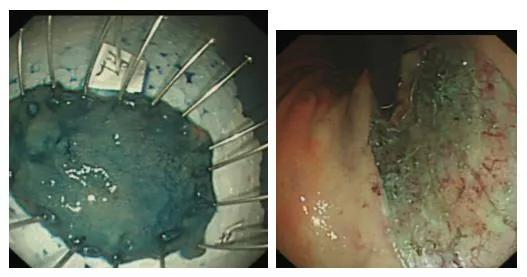

患者***,胃镜显示贲门粘膜病变、慢性非萎缩性胃炎。病理:(贲门)高级别上皮内瘤变。以"早期贲门癌"收入我科。于2020.8.4患者在气管插管全麻下行内镜下贲门粘膜剥离术。手术过程顺利,少量出血,剥离病灶后,止血钳处理创面。

术后嘱患者禁饮食,给予艾司奥美拉唑抑酸,硫糖铝保护胃粘膜等对症处理。2020-08-09患者在进食白菜梗及刺激性食物后出现呕血,黑便,测量血压95/65mmHg,伴有头晕、心悸、大汗。行急诊胃镜检查,镜下见胃底一长约2.5cm纵行裂口并新鲜出血,剥离创面下方可见一长约2.0cm纵行裂口,表面覆有血凝块并有新鲜渗血,分别钛夹闭合,并喷洒凝血酶溶液。